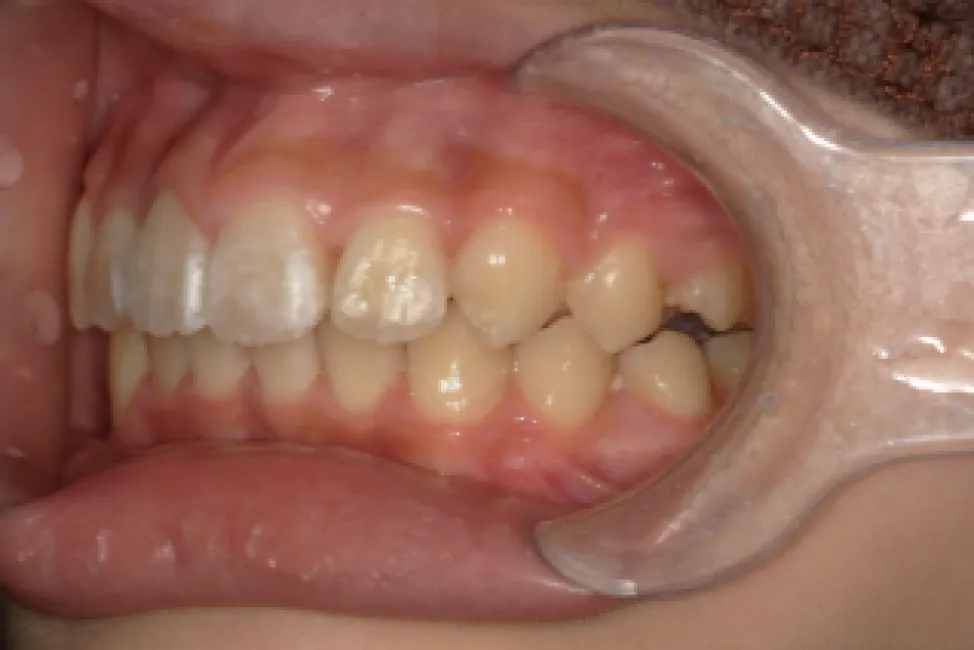

Before

After

性別

年齢

治療費用

治療内容

リスク

副作用

治療期間

男性

小学校高学年

902,000円

1年9か月

インビザライン

矯正治療の一般的なリスクといた

しましては、治療中のお痛み・歯

根吸収・歯肉退縮・治療後の後戻

りなどが生じる可能性があります。矯正治療は始めると、元の状態に

戻すのが難しいことがあります。